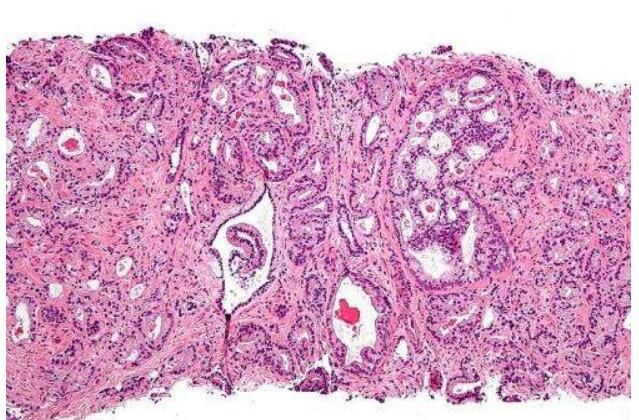

近日,一篇发表在国际杂志European Urology上题为“Pre-existing Castration-resistant Prostate Cancer–like Cells in Primary Prostate Cancer Promote Resistance to Hormonal Therapy”的研究报告中,来自杜克大学医学院等机构的科学家们通过研究识别出了一种能发现前列腺癌潜在隐患的分子特征。